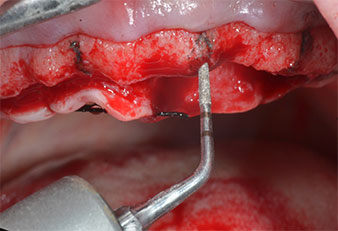

A flame-shaped, diamond-coated piezoelectric instrument (Piezomed I1) was used to mark the implant positions and to perform pilot preparation (Fig. 3). Care was taken to use an up and down movement, with reduced power, full irrigation and low pressure (below 300 g). Next a pilot instrument (Piezomed I2A/I2P) was applied for the initial 2 mm diameter enlargement of the implant sites (Fig. 4), followed by a 3 mm insert (Fig. 5).

In case of dense bone the whole instrument sequence including the intermediate instruments Piezomed Z25P and Z35P should be used to widen the osteotomies before the next enlargement step.

They are also indicated for preparation near the sinus membrane in connection with internal augmentation procedures or when there is less than 4 mm of residual bone height.

In the present case the Z25P and Z35P instruments were not used due to the relatively soft posterior bone, which was easily managed with the I3A/I3P.

Due to the relatively hard bone (D2) in this area, the 10 mm long implant sites at positions 11 and 21 were finalized with a 4 mm diameter rotary drill, in combination with a W&H WS-75 L surgical contra-angle handpiece, the W&H Implantmed implant motor and the optional W&H Osstell ISQ module. In contrast, due to the soft bone the posterior sites were prepared to a final 3 mm diameter using the Piezomed I3P instrument. The implants were finally placed transgingivally to osseointegrate for three months (Figs. 6-10). The existing denture was retained on four provisional implants (Fig. 8).